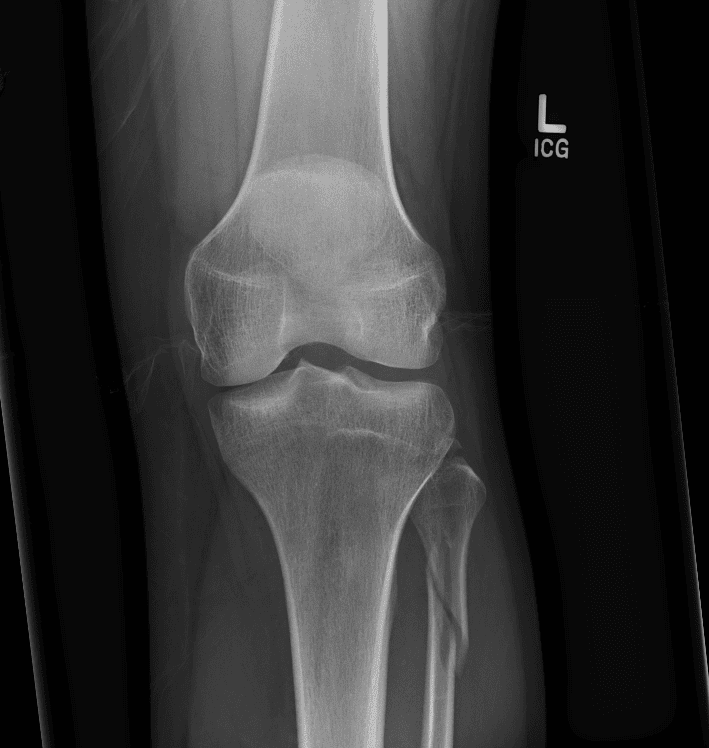

Simula o plantão incluindo casos sutis ou difíceis e alguns normais.